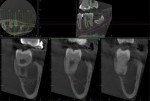

The parent informed the providers that a 3-dimensional CBCT scan was acquired at a previous dental office. This CBCT scan was thus requested and reviewed by a board-certified oral and maxillofacial radiologist who was part of the authors' team at MWU. The limited field-of-view CBCT scan, acquired on a Veraview X800 (J. Morita, morita.com), was received and showed teeth Nos. 17, 18, and the distal half of No. 19. Well-defined, circular, corticated, homogeneous radiolucency, approximately 12 mm x 8 mm x 9 mm, with no internal contents was observed on the buccal aspect of tooth No. 18 (Figure 3). Vertically, the radiolucency extended from the alveolar crest to the level of root apices. The roots of tooth No. 18 appeared to be displaced lingually, with a slight buccal inclination of the tooth crown. No displacement of the left mandibular canal was observed (Figure 4).